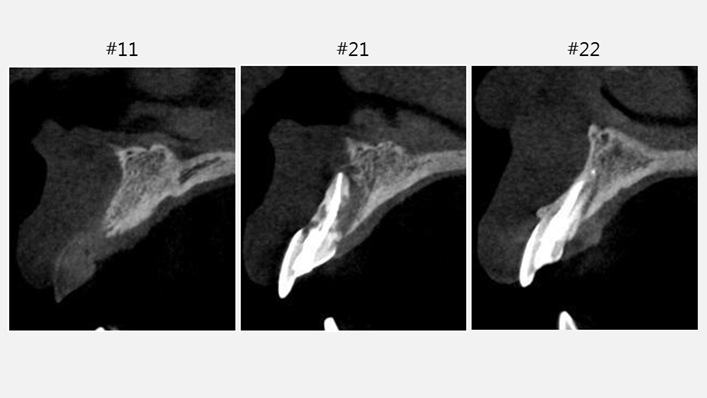

Clinical case: Patient-centered approach: treatment strategy for Root Membrane Technique & delayed implant placement

- Courtesy of Dr. Yoshiharu Hayashi, Japan -

Socket Shield Technique, anterior esthetics, maxillary anterior, esthetic, esthetics, delayed implant placement, socket preservation, AnyRidge, Root Membrane Kit, Root Membrane Technique, Partial Extraction Therapy, PET, esthetic zone, fuse abutment, Dr. Yoshiharu Hayashi,#11,#21,#22

AnyRidge implant system, fuse abutment Root membrane kit, PET Kit